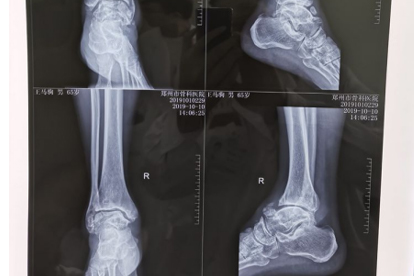

三、脚部疼痛或麻木

1、持续性疼痛:可能是关节炎、痛风或神经病变的征兆,尤其是夜间加重的疼痛。